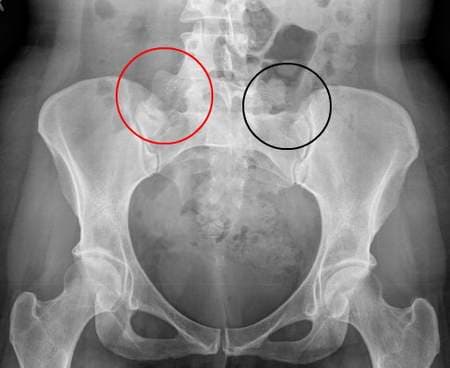

Theo các bác sĩ, bệnh viêm khớp háng thường khởi phát đột ngột. Các dấu hiệu nhận biết bệnh là: Sốt nhẹ hoặc sốt cao, đau ở vùng đùi hoặc đầu gối, cử động khớp háng khó khăn, dáng đi khập khiếng… Viêm khớp háng còn được đặc trưng bởi các hiện tượng bất thường như: Tràn dịch trong khớp, giãn rộng khe khớp, đường mỡ quanh khớp bị nén lại. Những hiện tượng này có thể được phát hiện thông qua chụp X- quang.Đến nay, y học vẫn chưa xác định được rõ nguyên nhân gây bệnh.Các bác sĩ cho biết, viêm khớp háng có thể do vi chấn thương lặp lại nhiều lần hoặc di virus.